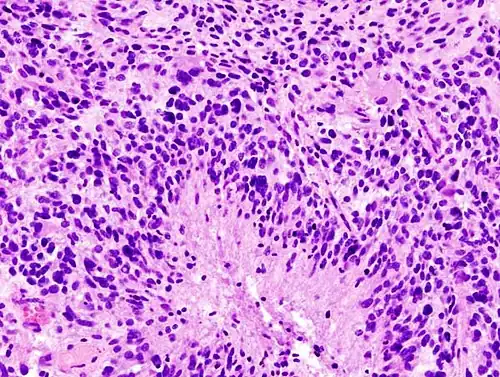

-

Histopathology of glioblastoma, showing high grade astrocytoma features of marked nuclear pleomorphism, multiple mitoses (one at white arrow) and multinucleated cells (one at black arrow), with cells having a patternless arrangement in a pink fibrillary background on H&E stain -

Lower magnification histopathology, showing necrosis surrounded by pseudopalisades of tumor cells, conferring a diagnosis of glioblastoma rather than anaplastic astrocytoma